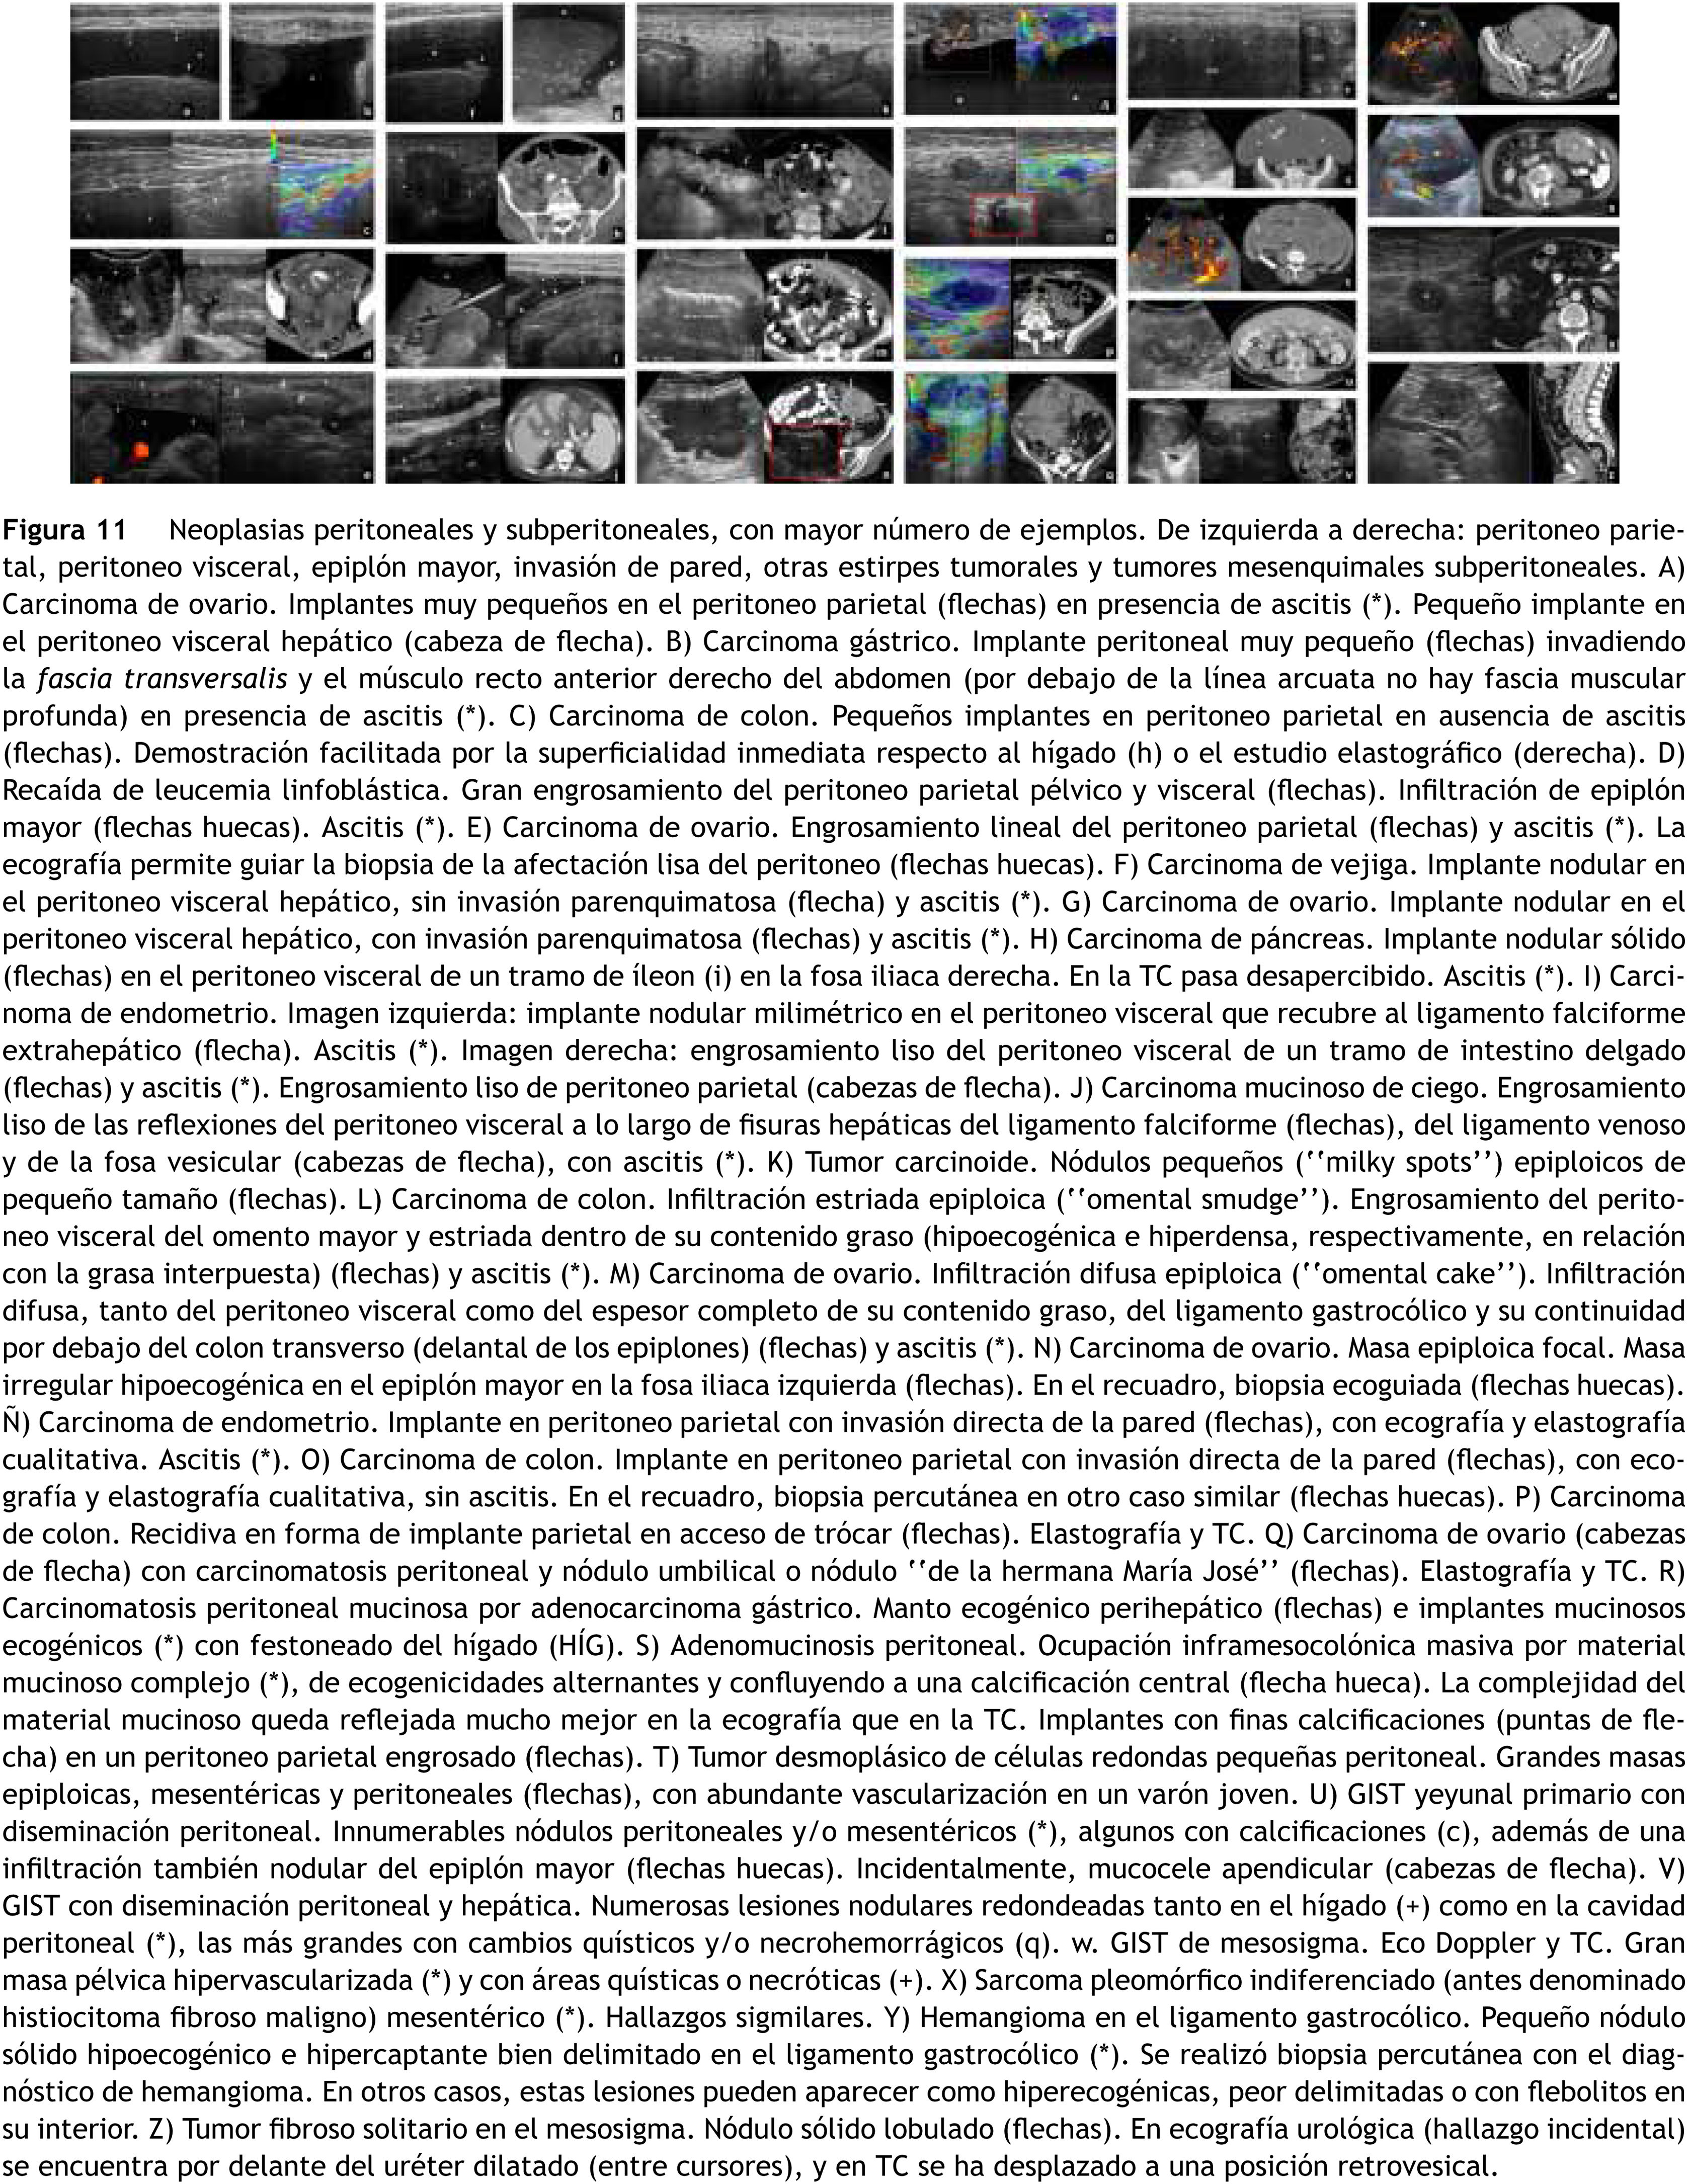

La ecografía es la técnica idónea para detectar ascitis y definirla como exudativa (con ecos, tabiques y loculaciones). Aunque exige experiencia y dedicación, es también extremadamente útil en el estudio de la carcinomatosis y otras formas de afectación neoplásica peritoneal, pudiendo demostrar implantes peritoneales incluso milimétricos y en ausencia de ascitis, engrosamiento más o menos nodular de las superficies peritoneales e infiltración del omento mayor, muy accesible por su situación anatómica, adherido o no al peritoneo parietal32,33. El contraste es más sensible que el Doppler en demostrar vascularización en zonas afectadas. En el omento realzan tanto las zonas ecogénicas como los nódulos hipoecoicos, estos con relleno radial y lavado más rápido. Es útil para diferenciar de tuberculosis (con menor realce) y seleccionar dónde biopsiar70,71.

Neoplasias peritoneales y subperitoneales. Recuadro verde: peritoneo parietal. Recuadro azul: peritoneo visceral. Recuadro morado: epiplón mayor. Recuadro rojo: invasión de pared. Recuadro amarillo: otras estirpes tumorales. Recuadro marrón: tumores mesenquimales subperitoneales. A) Carcinoma de ovario. Implantes muy pequeños en el peritoneo parietal (flechas) en presencia de ascitis (*). Pequeño implante en el peritoneo visceral hepático (cabeza de flecha). B) Carcinoma gástrico. Implante peritoneal muy pequeño (flechas) invadiendo la fascia transversalis y el músculo recto anterior derecho del abdomen (por debajo de la línea arcuata no hay fascia muscular profunda) en presencia de ascitis (*). C) Carcinoma de ovario. Engrosamiento lineal del peritoneo parietal (flechas) y ascitis (*). La ecografía permite guiar la biopsia de la afectación lisa del peritoneo (flechas huecas). D) Carcinoma de vejiga. Implante nodular en el peritoneo visceral hepático, sin invasión parenquimatosa (flecha) y ascitis (*). E) Carcinoma de ovario. Implante nodular en el peritoneo visceral hepático, con invasión parenquimatosa (flechas) y ascitis (*). F) Carcinoma de endometrio. Imagen izquierda: implante nodular milimétrico en el peritoneo visceral que recubre el ligamento falciforme extrahepático (flecha). Ascitis (*). Imagen derecha: engrosamiento liso del peritoneo visceral de un tramo de intestino delgado (flechas) y ascitis (*). Engrosamiento liso de peritoneo parietal (cabezas de flecha). G) Carcinoma de colon. Infiltración estriada epiploica (“omental smudge”). Engrosamiento del peritoneo visceral del omento mayor y estriada dentro de su contenido graso (hipoecogénica e hiperdensa, respectivamente, en relación con la grasa) (flechas) y ascitis (*). H) Carcinoma de ovario. Infiltración difusa epiploica (“omental cake”). Infiltración difusa del ligamento gastrocólico y su continuidad por debajo del colon transverso (delantal de los epiplones) (flechas) y ascitis (*). I) Carcinoma de colon. Implante en peritoneo parietal con invasión directa de la pared (flechas), con ecografía y elastografía cualitativa, sin ascitis. En el recuadro, biopsia percutánea en otro caso similar (flechas huecas). J) Tumor desmoplásico de células redondas pequeñas peritoneal. Grandes masas epiploicas, mesentéricas y peritoneales (flechas), con abundante vascularización en un varón joven. K) Carcinomatosis peritoneal mucinosa por adenocarcinoma gástrico. Manto ecogénico perihepático (flechas) e implantes mucinosos ecogénicos (*) con festoneado del hígado (HÍG). L) Adenomucinosis peritoneal. Ocupación inframesocolónica masiva por material mucinoso complejo (*), de ecogenicidades alternantes y confluyendo a una calcificación central (flecha hueca). La complejidad del material mucinoso queda reflejada mucho mejor en la ecografía que en la tomografía computarizada (TC). Implantes con finas calcificaciones (puntas de flecha) en un peritoneo parietal engrosado (flechas). M) GIST con diseminación peritoneal y hepática. Numerosas lesiones nodulares redondeadas tanto en el hígado (+) como en la cavidad peritoneal (*), las más grandes con cambios quísticos y/o necrohemorrágicos (q). N) GIST de mesosigma. Eco-Doppler y TC. Gran masa pélvica hipervascularizada (*) y con áreas quísticas o necróticas (+).

Los hallazgos en el mesotelioma y carcinoma seroso primario, así como en la linfomatosis peritoneal, son similares con matices. El tumor desmoplásico de células redondas pequeñas afecta con mal pronóstico a varones jóvenes en forma de una o múltiples masas sólidas heterogéneas, con o sin ascitis33.

El pseudomixoma peritoneal es el relleno de la cavidad peritoneal por material mucinoso, casi siempre por rotura de un mucocele apendicular. Ecográficamente se comporta como una ocupación con ecogenicidades diversas, ocasionalmente alternantes, con calcificaciones, nódulos o manto peritoneal ecogénico y festoneado visceral.

Numerosas neoplasias mesenquimales pueden afectar al mesenterio o los epiplones, comportándose como masas sólidas con tendencia a ser mayores, más heterogéneas e infiltrantes en las variantes malignas33.